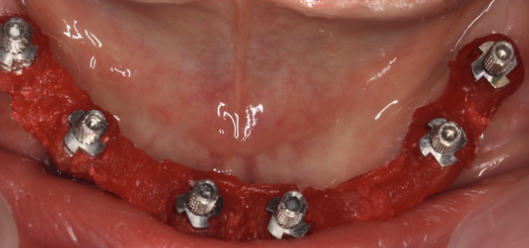

Etapa 2: Descoperirea implanturilor

Gingia se decupează și în implant se înșurubează bonturile de vindecare. Aceste bonturi, diferite de cele protetice, sunt șuruburi care se montează pentru o perioadă de aproximativ 14 zile pentru a ajuta la vindecarea și conformarea gingiei și crearea unui manșon în jurul bontului protetic. După această perioadă ele se îndepărtează.